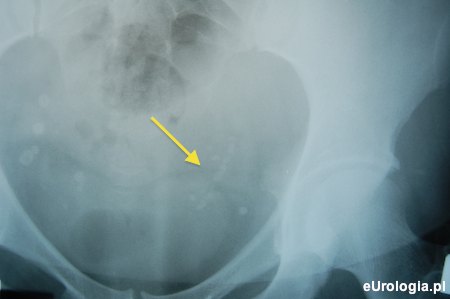

Fot. RTG przeglądowe z widoczną drogą kamiczą dolnego odcinka lewego moczowodu

Droga kamicza jest szczególnym rodzajem kamicy moczowodowej, która powstaje w wyniku przemieszczenia się fragmentów rokruszonego podczas ESWL złogu nerkowego do moczowodu. Droga kamicza zbudowana jest z drobnych kawałków złogu ułożonych jeden za drugim.